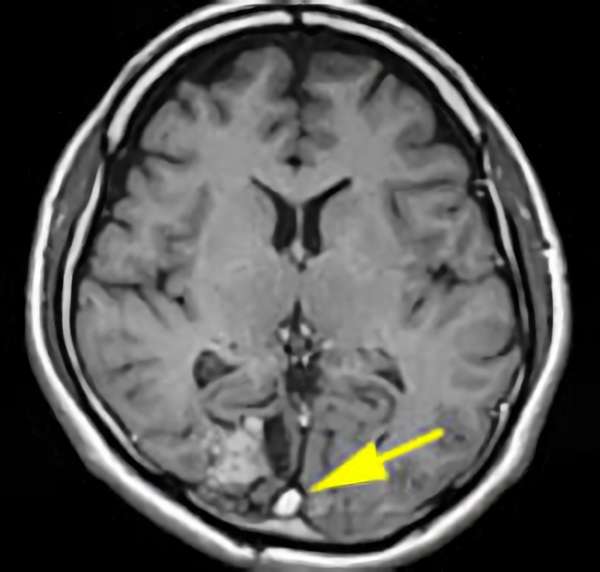

'25年10月

40代

南田,野本,元永

脳幹部

海綿状血管腫

出血の予防目的

熊本県の病院

No.No.62 手術前1

No.No.62 手術前2

No.No.62 手術後1

No.No.62 手術後2

No.No.62 摘出前

No.No.62 摘出中1

No.No.62 摘出中2

No.No.62 摘出後

CT/MRにより完全に摘出されたことが確認された